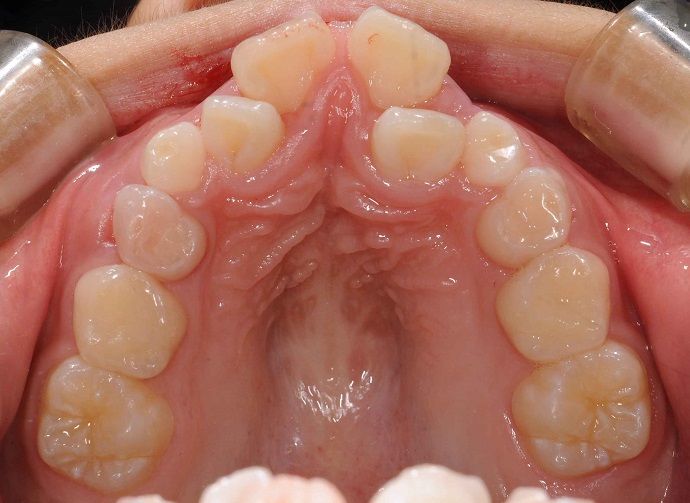

写真は極端な例ですが、このように高口蓋(これは骨のひずみです)を呈するケースはとても多いでしょう?

高口蓋の状態で機能訓練をするのは、ある意味

舌を変形させないと入らないでしょう?

また、こういった場合、その舌は必ず奥と下方に押し込められて機能訓練には不利な状況なのですから、相当無理なことを強要しているのです。